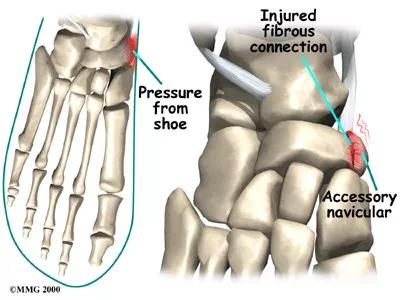

1.足部扭伤时,副舟骨与舟骨稳定的纤维软骨连接受到破坏而出现不稳定,下地负重时,胫后肌腱牵拉副舟骨时,受伤的纤维软骨连结也收到牵拉而引起疼痛。

这种是最常见的情况,所以很多人足踝扭伤以后,踝关节内外侧韧带损伤很快恢复了,但是足内侧长期疼痛,往往就是这个原因。

II型被称为假关节型,副舟骨与舟骨以纤维软骨相连,被称为“两分舟骨”,可引发疼痛;